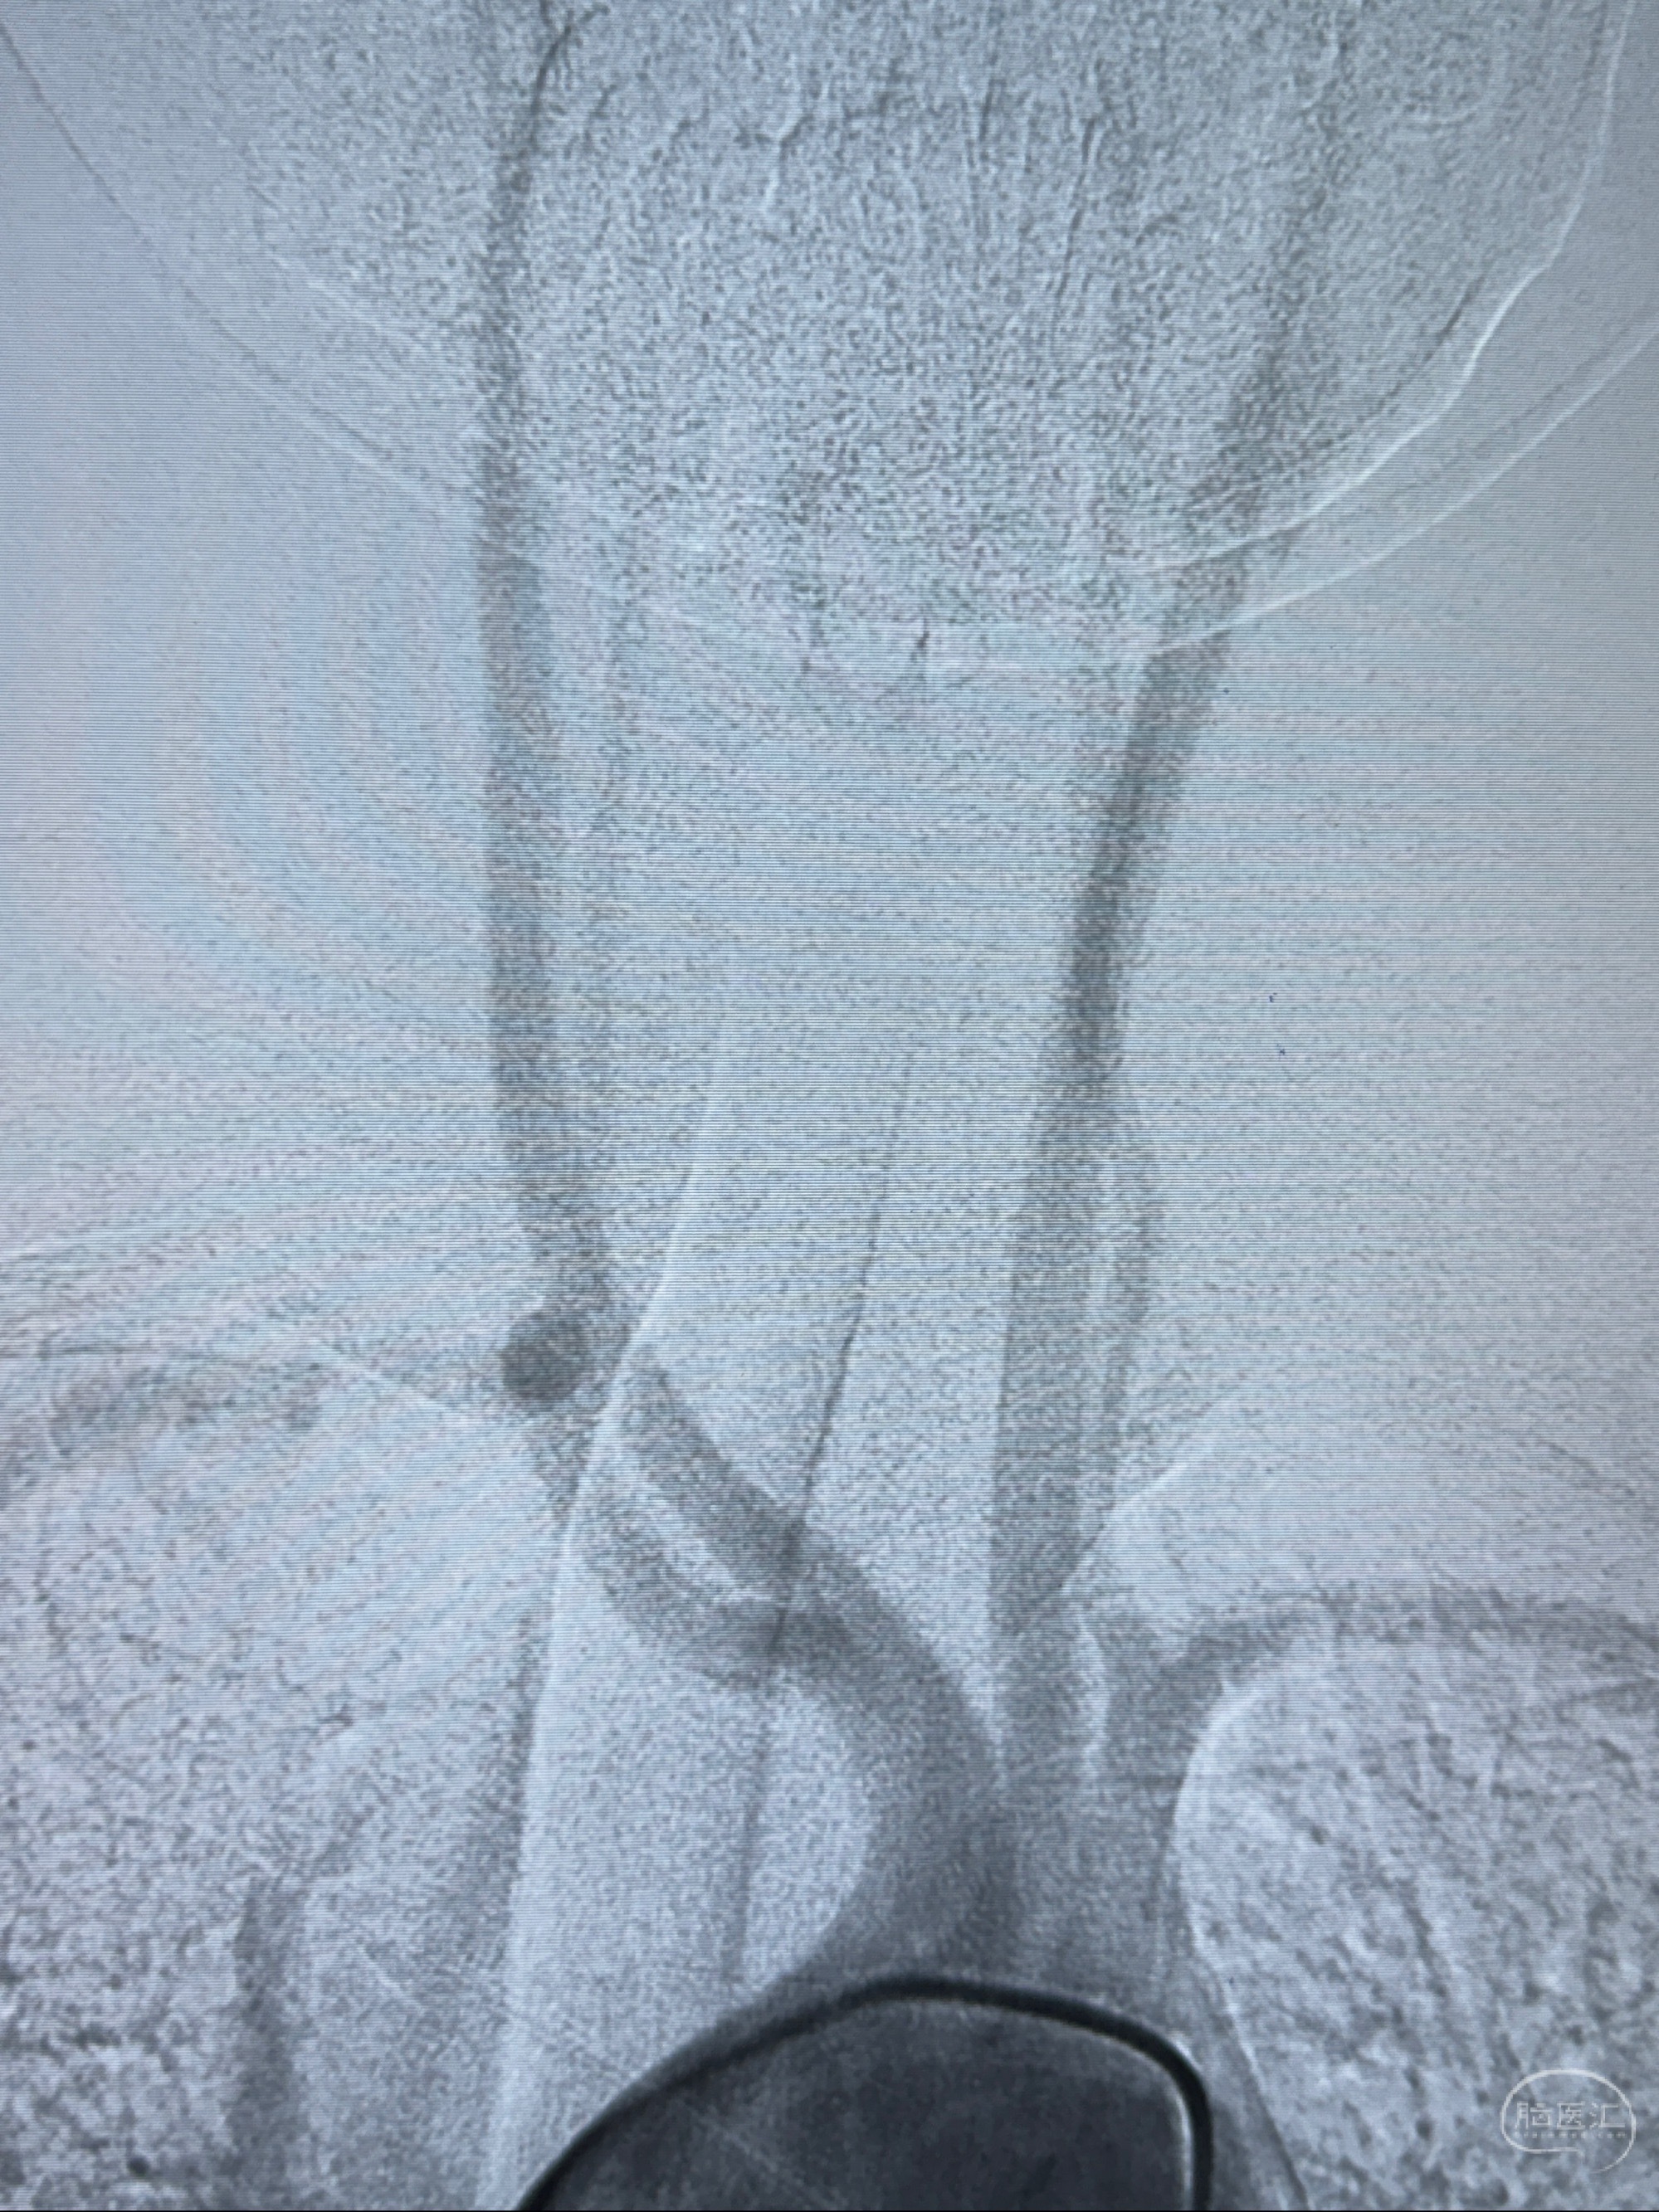

2023-11-01 蓝十字脑科医院 头颅MRI+DWI+MRA:左侧枕叶皮层下小斑片缺血或变性灶,右侧大脑前动脉A1段毛糙,显影淡、纤细,建议完善CTA;

2023-11-03 蓝十字脑科医院 头颅CTA:左侧颈内动脉C6段微小动脉瘤可能(约2mm),右侧大脑前动脉A1段纤细(对侧优势),左侧大脑中动脉提前分叉。

1.左侧颈内动脉瘤